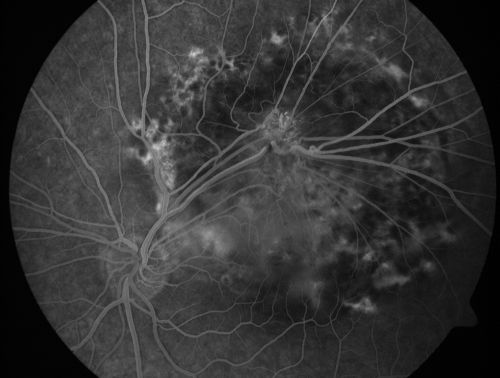

Retinal Pigment Epithelial Dysgenesis